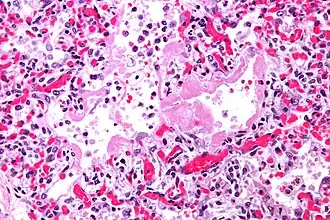

"Золотым" стандартом диагностики ОИП является биопсия легких[3].